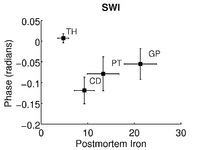

Quantifying magnetic susceptibility in the brain from the phase of the MR signal provides a non-invasive means for measuring the accumulation of iron believed to occur with aging and neurodegenerative disease. Phase observations from local susceptibility distributions, however, are corrupted by external biasfields, which may be identical to the sources of interest. Furthermore, limited observations of the phase makes the inversion ill-posed. We describe a variational approach to susceptibility estimation that incorporates a tissue-air atlas to resolve ambiguity in the forward model, while eliminating additional biasfields through application of the Laplacian. Results show qualitative improvement over two methods commonly used to infer underlying susceptibility values, and quantitative susceptibility estimates show better correlation with postmortem iron concentrations than competing methods.

Results